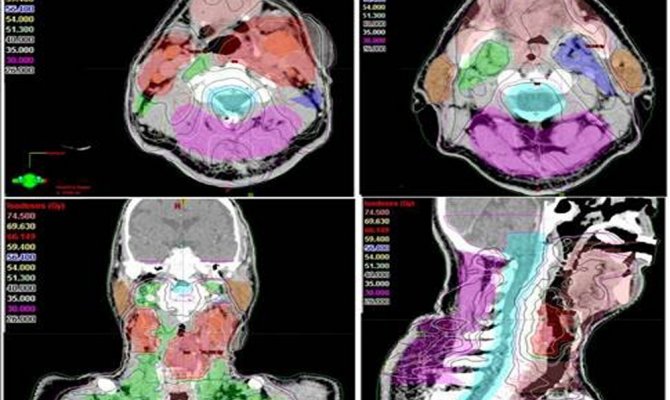

Antalya'da kanser kliniği uzmanlarından Radyasyon Onkolojisi Prof. Dr. Ali Aydın Yavuz, kanser hastalarının radyoterapisi sırasında "Yapay Zeka" uygulamalarının kanserde tedavi başarısını arttırdığını belirtti. Son yıllarda yapay zeka uygulamalarının kanser alanında kullanılmasına yönelik araştırmalarda artış olduğunu ifade eden Prof. Dr. Yavuz, "Tümör ve çevredeki normal dokuların üç boyutlu olarak sınırlarının çizildiği bu süreç, bir hastanın tümör bölgesine ne kadar radyasyon alacağını ve ışının en uygun nasıl odaklanacağını belirler. Özellikle ABD'nin Ulusal Sağlık Enstitüsünce desteklenen önemli bir araştırma projesinde "Yapay Zeka" kullanarak yüksek riskli tümör hedef hacimlerinin sınırlarının 3 boyutlu olarak belirlenmesi için her bir görüntüleme film kesitinde tümör ve normal doku sınırlarının tek tek çizilmesi (konturlama) işlemlerini otomatikleştirmek için yeni bir yöntem geliştirildi" dedi.

Bu çalışmanın sadece yüksek riskli tümör hacimlerinin "Yapay Zeka" ile otomatik bir şekilde ve çok yüksek doğrulukta belirlenmesine yönelik olduğunu dile getiren Prof. Dr. Yavuz, "Bir sonraki aşamada, eldeki tüm veriler birleştirilerek, orta ve düşük riskli tümör bölgelerinin de otomatik ve en doğru bir şekilde belirlenmesi mümkün olabileceği gibi, hastaya özgü en uygun radyoterapi veya kemoterapiyi de ayarlamak adına çeşitli genetik mutasyonlara ait bilgiler de bu yapay zeka uygulamasına entegre edilebilecektir. Bu şekilde, kanser tedavisi sonuçlarında başarı oranlarının artması da kaçınılmazdır. Yöntemin çok önemli bir avantajı da bizlere sunduğu yüksek hız ve verimliliktir. Normalde, örneğin bir baş boyun kanserinde, hedeflenen hacimleri belirlemek bir hekimin 1-4 saatini alır. Yapay Zeka kullanan özel bilgisayar sistemi ile hem bir dakikadan kısa bir sürede hedef hacimler belirlenebilmekte, hem de hekimden hekime değişebilen hata payları ihtimali tümüyle ortadan kalkmaktadır. Bu yöntem, özellikle, hedef hacim belirleme alanında tecrübeli uzman sayısının daha az olduğu düşük ve orta gelir düzeyindeki ülkelerde çok büyük bir kolaylık sağlayacaktır, ancak bu yöntemin ABD gibi gelişmiş ülkelerde de kanser tedavilerindeki yararlılık ve verimliliği çok artıracağı açıktır" şeklinde konuştu.